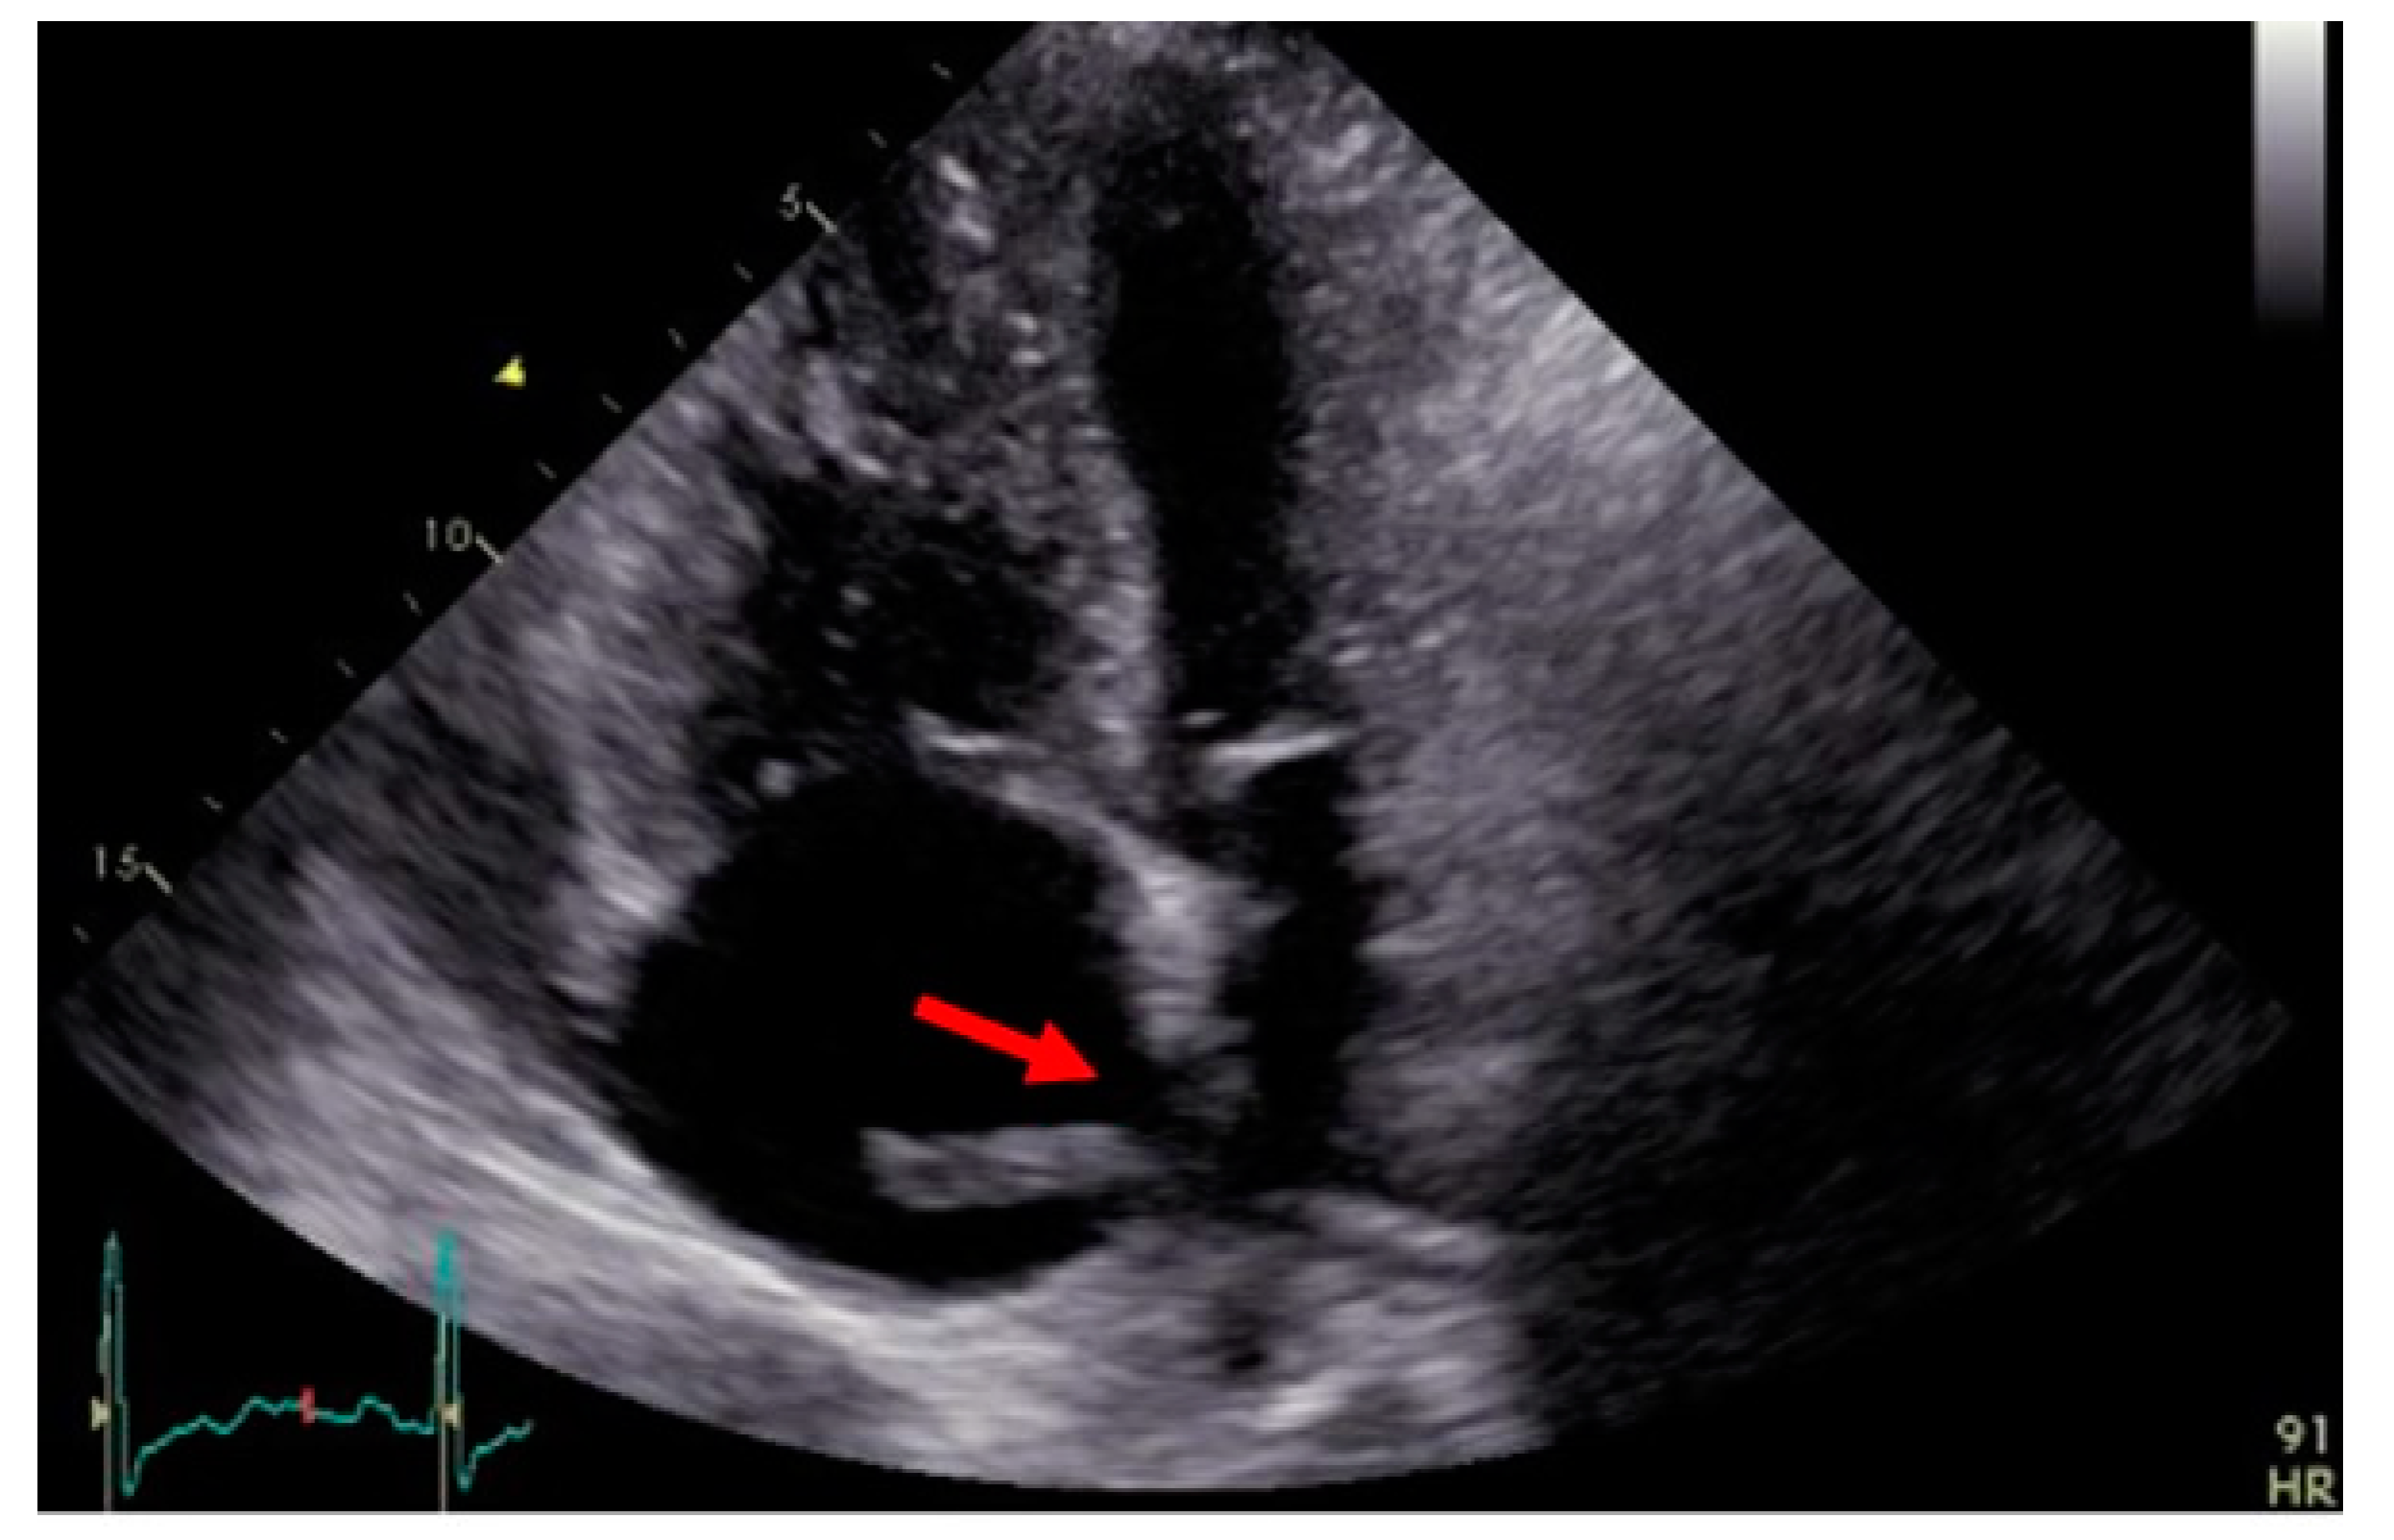

2.2. Case 2

3.5. Transthoracic Echocardiography